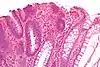

| Hyperplasique | Cryptes dentées non-ramifiées | Non | ![]() |

Hyperplasique polypose syndrome | |